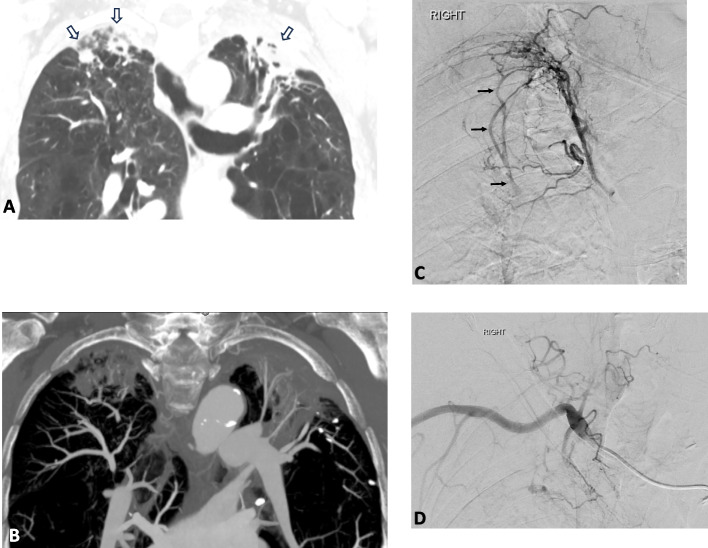

Abstract Image